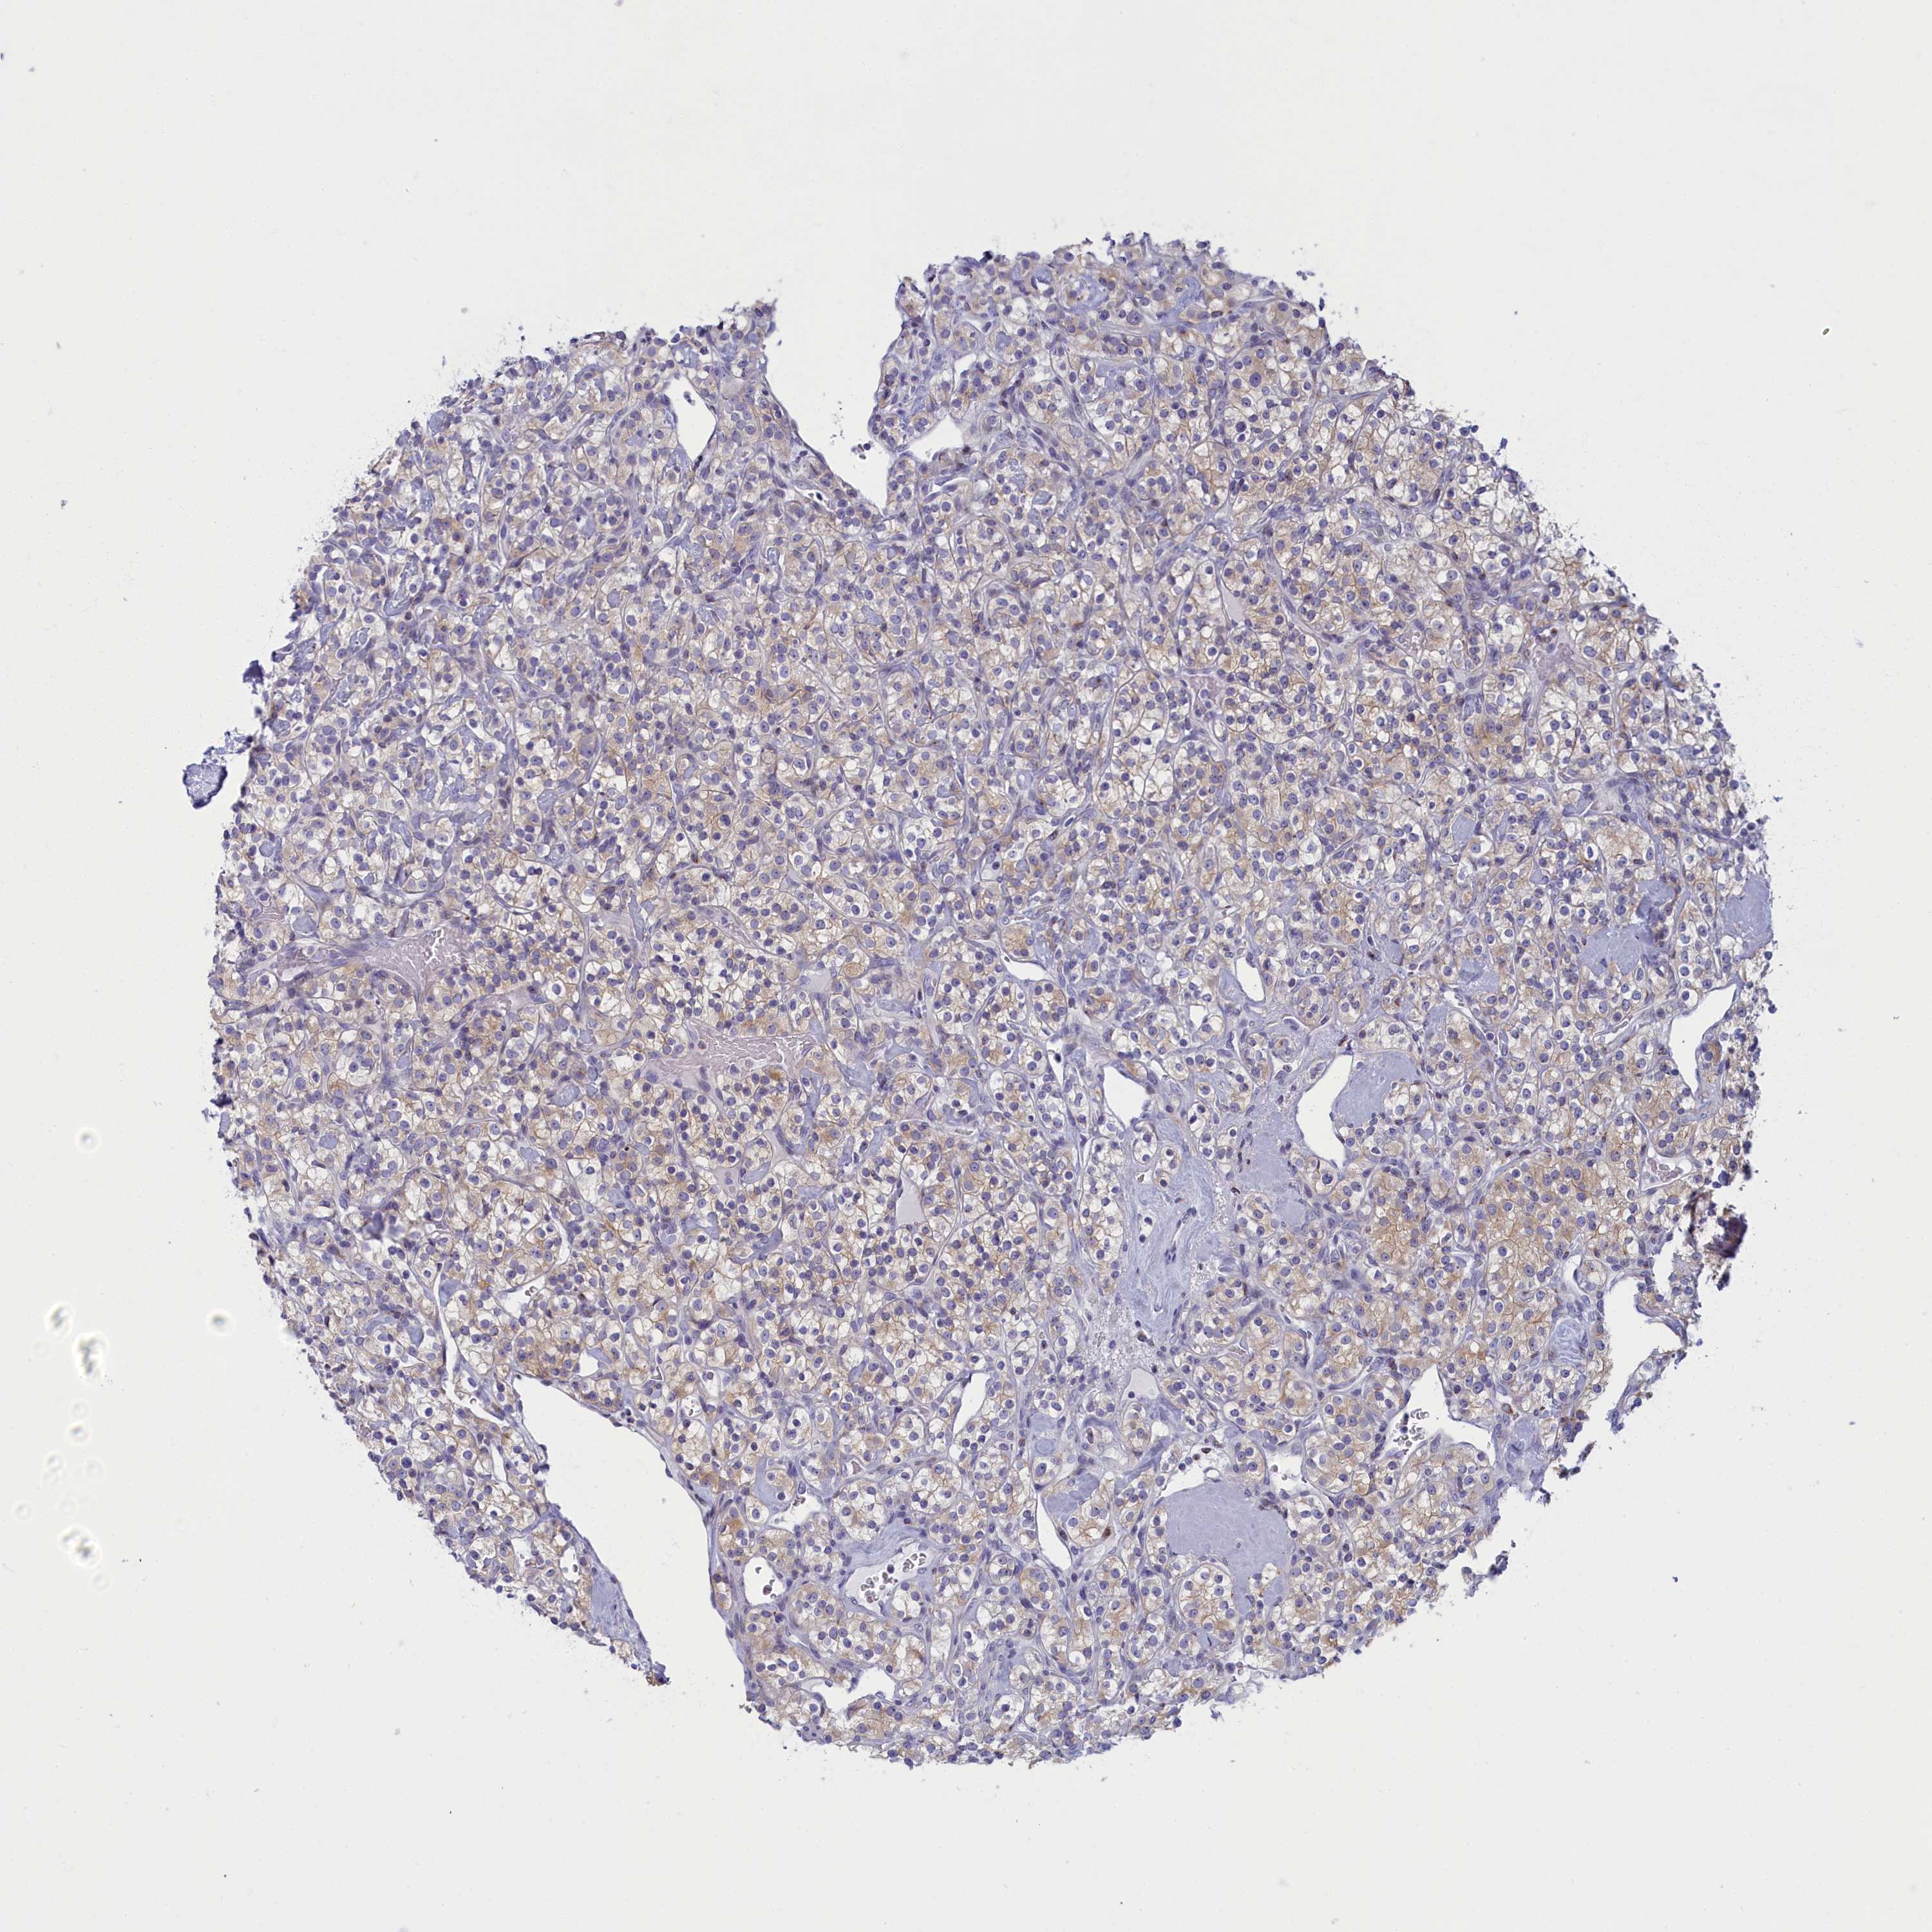

KIDNEY RENAL CLEAR CELL CARCINOMA (VALIDATION) - Interactive survival scatter ploti

The Survival Scatter plot shows the clinical status (i.e. dead or alive) for all individuals in the patient cohort, based on the same data that underlies the corresponding Kaplan-Meier plots. Patients that are alive at last time for follow-up are shown in blue and patients who have died during the study are shown in red.

The x-axis shows the expression levels (FPKM) of the investigated gene in the tumor tissue at the time of diagnosis. The y-axis shows the follow-up time after diagnosis (years). Both axes are complimented with kernel density curves demonstrating the data density over the axes. The top density plot shows the expression levels (FPKM) distribution among dead (red) and alive patients (blue). The right density plot shows the data density of the survived years of dead patients with high and low expression levels respectively, stratified using the cutoff indicated by the vertical dashed line through the Survival Scatter plot. This cutoff is automatically defined based on the FPKM cutoff that minimizes the p-score. The cutoff can be changed by dragging the vertical line or by entering a cutoff value in the square labeled "Current cut-off".

Under the Survival Scatter plot the p-score landscape (black curve; left axis) is shown together with dead median separation (red curve; right axis). Dead median separation is the difference in median mRNA expression between patients who have died with high and low expression, respectively. It is calculated as follows: median FPKM expression of dead patients with high expression - median FPKM expression of dead patients with low expression. This is intended to aid the user in visually exploring custom cutoffs and the associated p-scores and dead median separation.

Individual patient data is displayed and can be filtered by clicking on one or more of the category buttons on the top of the page. Categories describing expression level and patient information include: high, low, alive, dead, female, male and tumor stages. The scale of the x-axis can be toggled between linear and log-scale by clicking on the "x log" button. Mouse-over function shows TCGA ID, patient information and mRNA expression (FPKM) for each patient.

& Survival analysisi

Kaplan-Meier plots summarize results from analysis of correlation between mRNA expression level and patient survival. Patients were divided based on level of expression into one of the two groups "low" (under cut off) or "high" (over cut off). X-axis shows time for survival (years) and y-axis shows the probability of survival, where 1.0 corresponds to 100 percent.

NOL10 is not prognostic in Kidney Renal Clear Cell Carcinoma (validation)

: 13.09

Average pTPM 14.6

Number of samples 100